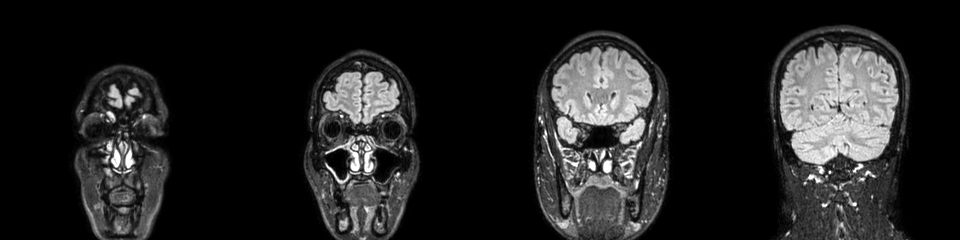

Córtex pré-frontal, ou mais precisamente córtex orbitofrontal, é o nome de uma das regiões do cérebro onde muitos cientistas procuram os possíveis sinais da confiança. Fica mesmo atrás dos nossos olhos. Aparentemente, essa é uma das zonas onde será possível observar os disparos dos nossos neurónios quando estão envolvidos numa decisão que tomamos com confiança. Mas, seguramente, não será a única. As imagens da ressonância magnética de Nelson Évora mostram um bonito cérebro a preto e branco, mas, para já, não nos dão pistas sobre a sua confiança. Resta-nos confiar nas suas palavras.

Zachary Mainen é coordenador de uma equipa de investigadores do Programa de Neurociências da Fundação Champalimaud. Antes da realização da ressonância magnética, Zachary explicou a Nelson Évora que seria impossível tirar alguma conclusão do exame.

Nelson Évora tem razão. Para que se conseguisse ver alguma coisa, era preciso que o atleta olímpico fosse submetido a vários testes que colocassem a sua confiança à prova. No limite, poderíamos apontar a nossa atenção para algum alvo específico (uma região do cérebro) e ver umas áreas a ficar marcadas a vermelho. A cor indicaria a actividade cerebral e denunciaria se os neurónios estavam ou não a disparar com maior ou menor intensidade, mais ou menos velocidade. Mas a verdade é que não seríamos capazes de sequer perceber inteiramente o que estávamos a ver. É isso que nos diz Zachary Mainen, que olhou para o resultado do exame simples de Nelson Évora e concluiu que não é possível dizer nada sobre a sua confiança. Mas o atleta dá uma ajuda ao cientista.

Zachary Mainen é um dos muitos investigadores que querem saber mais. Apesar dos avanços nas técnicas de imagens que nos permitem hoje espreitar para dentro dos nossos cérebros e decifrar coisas absolutamente incríveis, falta aprender muito. “No laboratório, em animais, observámos neurónios individuais, células individuais. Quando olhamos para uma ressonância magnética, olhamos para milhões de células ao mesmo tempo. Surpreendentemente, já é o suficiente para retirar informações fantásticas. Somos, por exemplo, capazes de dizer, olhando imagens e analisando dados, em que é que alguém está a pensar. Um objecto. Isso já é possível. Somos constantemente surpreendidos com o que se consegue fazer com estas técnicas. Embora a informação seja ainda muito crua, os métodos de análise são hoje muito sofisticados e rápidos”, constata.